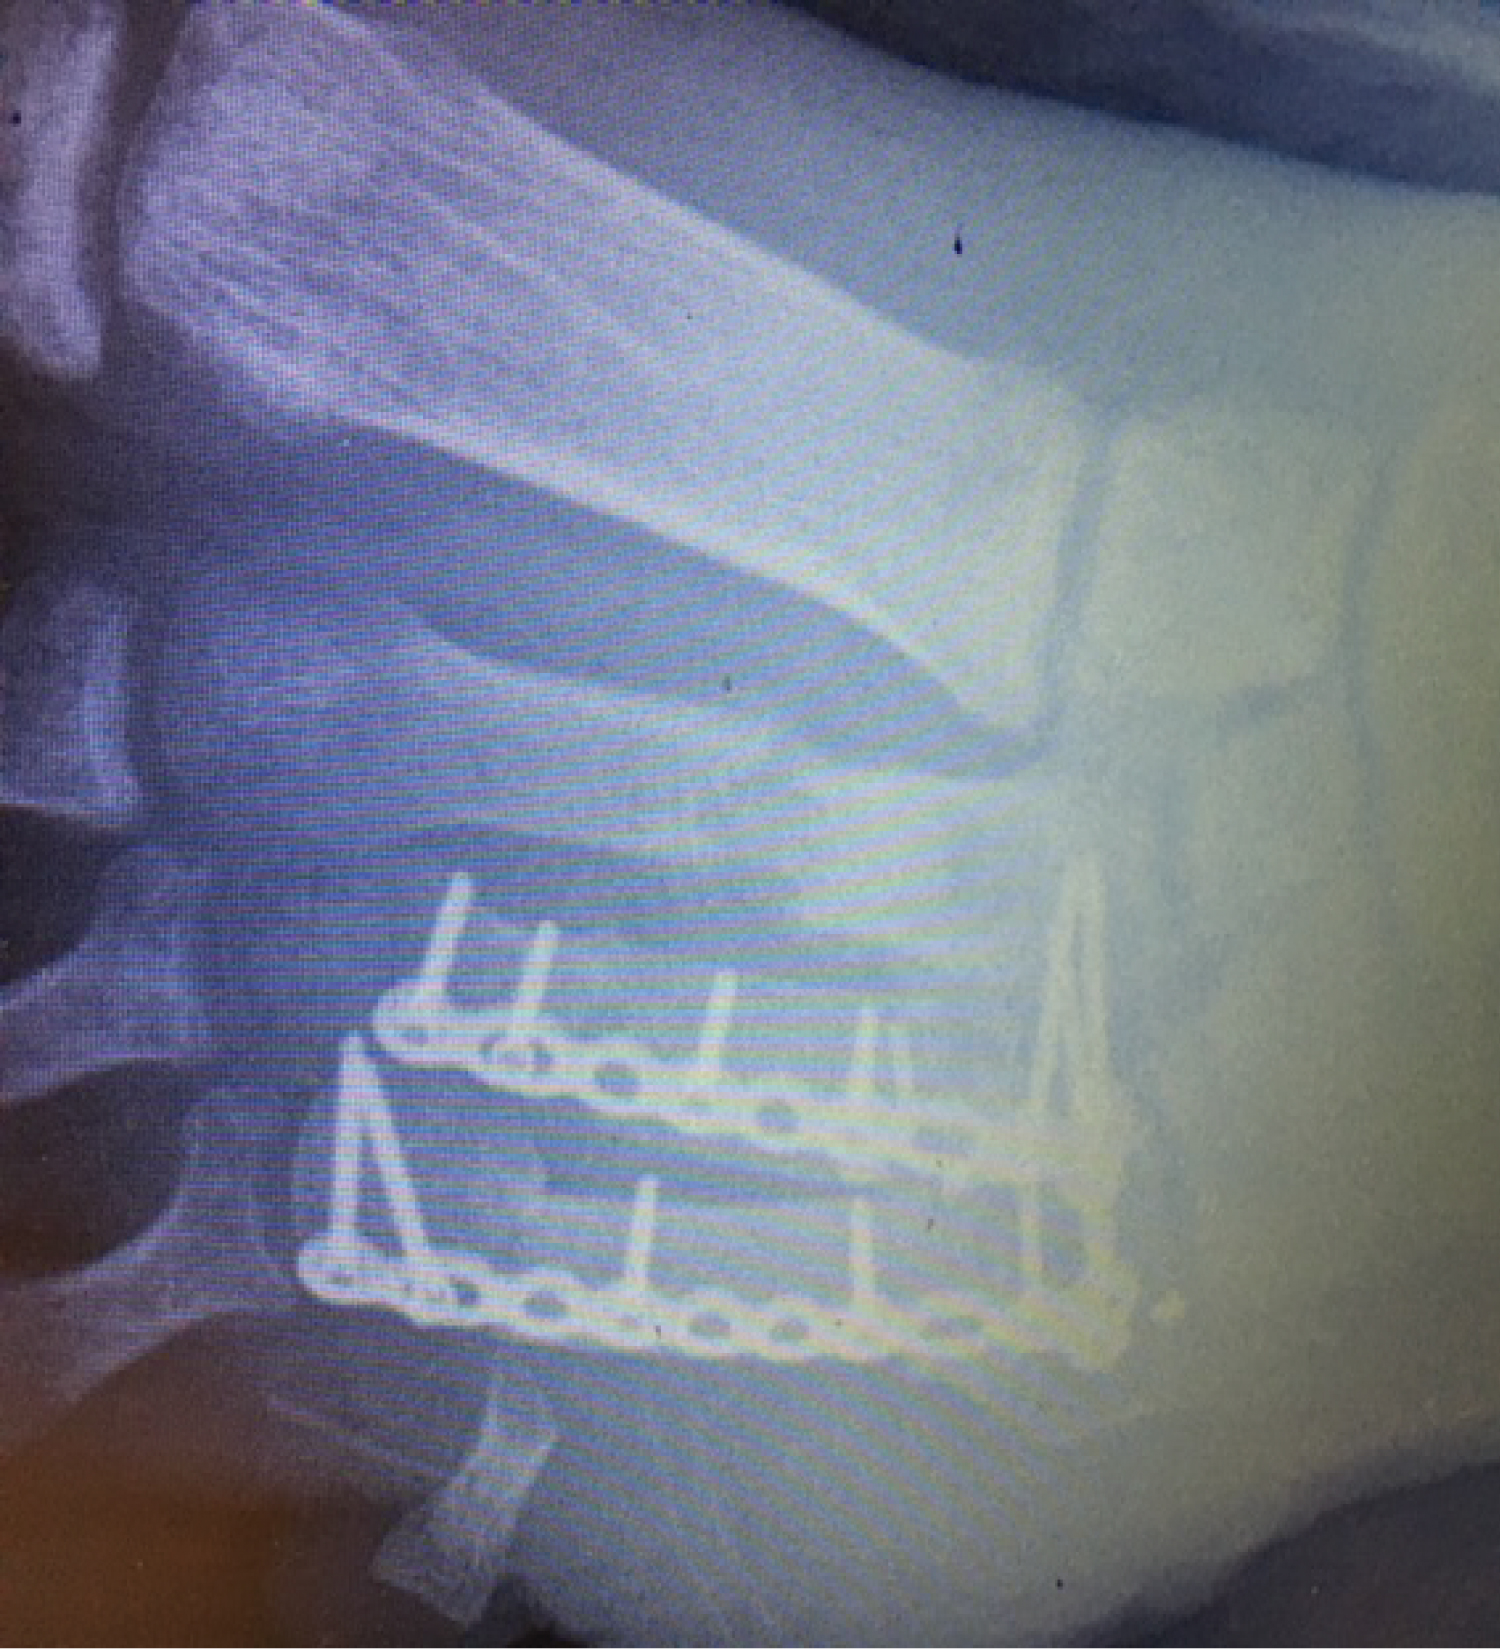

A good approximation of the metatarsal head cascade was demonstrated radiographically. We used the Arthrex® foot plating system to secure the bone graft with locking screws into the metatarsal head, metatarsal base and screws to secure the graft onto the plate (Figure 6). Stable fixation was confirmed by clinical examination on the operating table and with intraoperative fluoroscopic pictures. The wound was thoroughly irrigated and the flap was closed with interrupted non-absorbable sutures.

Figure 6: Intra-operative picture of graft fixation. View Figure 6

His flap healed uneventfully within 2 weeks and his radiographs were satisfactory (Figure 7 and Figure 8). He was comfortable enough to partially weight bear in a full cast avoiding any forefoot loading at that stage.

Figure 8: radiograph at 2 weeks. View Figure 8

His radiographs at 6 weeks showed that the bone had united (Figure 9) and he was able to comfortably fully weight bear (see Video in appendix) with normal footwear.

Figure 9: Rib graft union at 6 weeks. View Figure 9